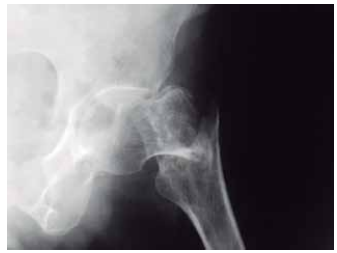

Para um diagnóstico preciso, as radiografias podem ser realizadas em diferentes posições.

Observe a imagem a seguir:

Enunciado 4560249-1

(Arquivo pessoal; imagem usada com autorização)

A imagem contempla a região coxofemural, realizada em posicionamento anteroposterior, e refere-se a um(a)